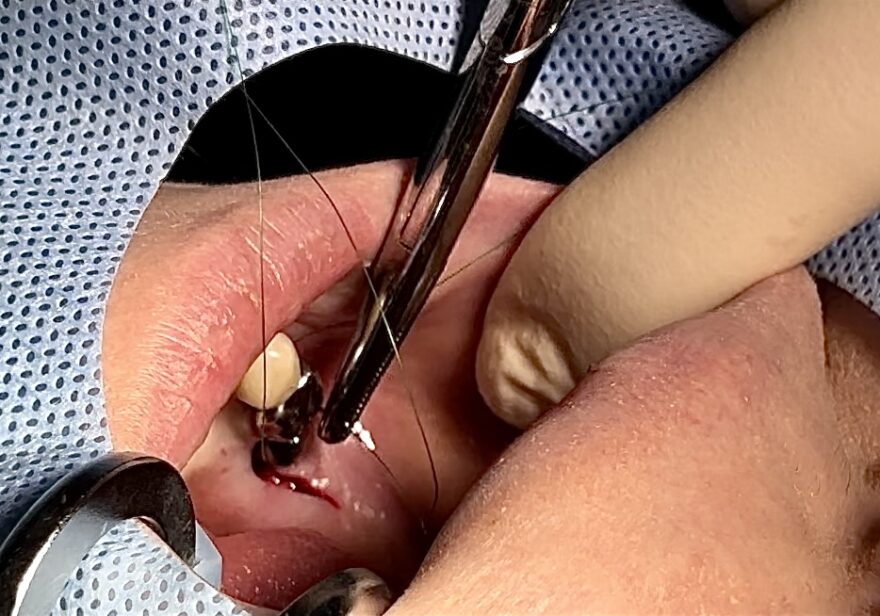

縫合して終了!

インプラント埋入後は傷口を縫合して終了です。

傷口はたったこれだけ!!

「もう終わったんですか?」と驚かれる患者さまも多くいらっしゃいます。

ここまで、音や振動はありますが、局所麻酔が効いているため痛みはほぼありません。

音や振動も苦手という場合には、麻酔科医による静脈内鎮静法(リラックス麻酔)を行うことも可能です。